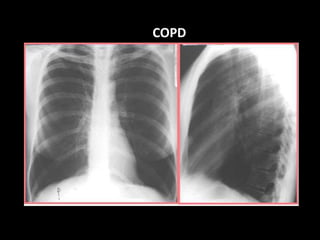

COPD